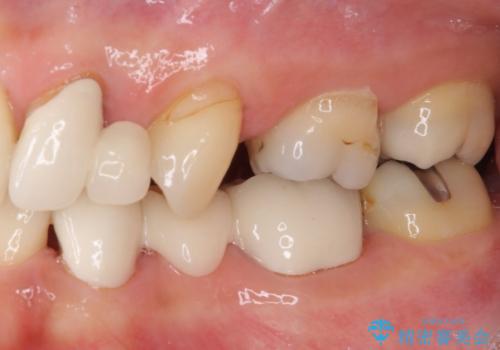

- 残存している乳歯や欠損部の隙間を気にして来院された患者様です。

上顎は左右ともに小臼歯が欠損しており、右側は乳前歯が残っている状態でした。

ブリッジによる補綴治療にて、欠損や隙間を補完することとしましたが、神経を取り除いたり、審美的に不自然になることを避けるため、部分矯正を併用することとしました。

乳歯は事前に抜歯することとしました。